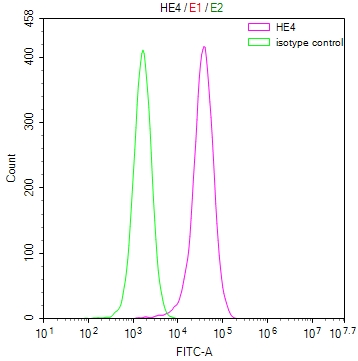

The image on the left is immunohistochemistry of paraffin-embedded Human gastic cancer tissue using CSB-PA051152(CYP2D6 Antibody) at dilution 1/30, on the right is treated with synthetic peptide. (Original magnification: ×200)